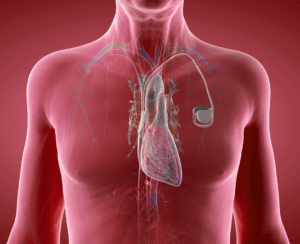

Un marcapasos es un dispositivo pequeño pero esencial para corregir los latidos cardíacos lentos o irregulares.

Un marcapasos es un dispositivo pequeño pero esencial para corregir los latidos cardíacos lentos o irregulares.

Un marcapasos es un dispositivo pequeño pero esencial para corregir los latidos cardíacos lentos o irregulares.

Un marcapasos es un dispositivo pequeño pero esencial para corregir los latidos cardíacos lentos o irregulares.

Un marcapasos es un dispositivo pequeño pero esencial para corregir los latidos cardíacos lentos o irregulares.